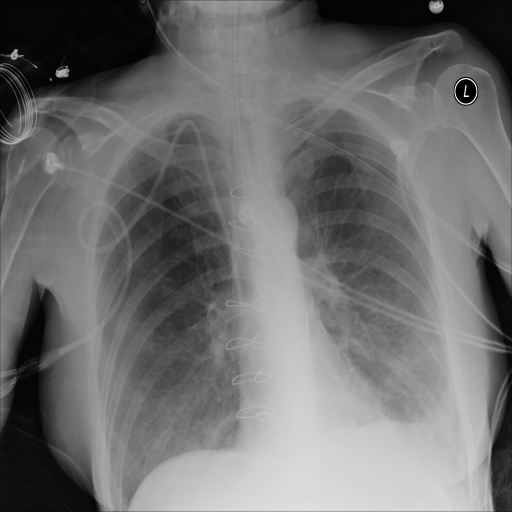

In Fig. 1, we show four ϵitalic-ϵ\epsilon-LDP-processed CXR images of clinical cases obtained with the image domain LDP, which directly imposes the Laplace mechanism on the input image, with different privacy budgets together with the original images. Fig. 2 shows four ϵitalic-ϵ\epsilon-LDP-processed CXR images of clinical cases obtained with DP-GLOW and different privacy budgets together with the original images. In case 1 for DP-GLOW, there is decreased permeability in the bilateral hilar regions. Although this hilar opacity tends to be preserved with a larger privacy budget, the entire image is degraded when the privacy budget becomes 101HWsuperscript101𝐻𝑊10^{1}\cdot H\cdot W. A similar tendency is observed in the images of all the four cases for DP-GLOW; for example, in case 4 with ϵ=101HWitalic-ϵsuperscript101𝐻𝑊\epsilon=10^{1}\cdot H\cdot W, the lung opacity suggesting pneumonia in the right lower lung field is well preserved, while the entire image is degraded.

Refer to caption

(a) Original

case 1

(b) ϵ=103HWitalic-ϵsuperscript103𝐻𝑊\epsilon=10^{3}\cdot H\cdot W

(c) ϵ=102HWitalic-ϵsuperscript102𝐻𝑊\epsilon=10^{2}\cdot H\cdot W

(d) ϵ=101HWitalic-ϵsuperscript101𝐻𝑊\epsilon=10^{1}\cdot H\cdot W

Figure 2: ϵitalic-ϵ\epsilon-LDP-processed CXR images obtained with DP-GLOW.